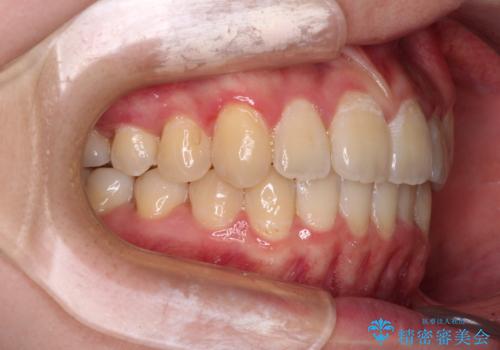

- 前歯のデコボコと八重歯を気にして来院された患者様です。

インビザラインでの治療を希望されていましたが、前歯のクロスバイトや下顎小臼歯の捻転が認められたため、インビザライン単独で治療を行うよりも、ワイヤー装置を併用した方が、治療期間の短縮やトラブル回避できると判断し、ワイヤー装置を併用することとしました。

まずはワイヤー装置により前歯のクロスバイトと下顎小臼歯の捻転を改善し、その後インビザラインにより全体を整える矯正治療を行うこととしました。

前歯のクロスバイトは、インビザラインでの改善中に前歯に過剰な力がかかり、歯髄壊死や歯肉退縮を引き起こすことがあります。また下顎小臼歯は寸胴型のため、捻転を排除することが難しいことが知られています。

それをワイヤー装置にて速やかに改善することで、トータルでの治療期間を短くすることができます。